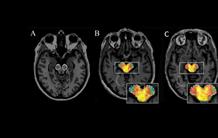

Augmentation de la

neuroinflammation dans la substance noire chez un patient atteint de la maladie

de Parkinson par rapport à un sujet sain : A : IRM représentative

montrant la délimitation faite au niveau de la substance noire (droite et

gauche) pour analyser la fixation du [18F]-DPA714 dans cette région. B : sur le même plan de

coupe, superposition de l’IRM et de l’image TEP [18F]-DPA714 chez un

sujet sain. On voit dans la région de la substance noire bilatérale qu’il y a

très peu de fixation du radiotraceur. C : Chez un sujet atteint de

la maladie de Parkinson représentatif de l’étude, la fixation du traceur est

augmentée du côté le plus atteint, c’est-à-dire du côté opposé à celui présentant

les symptômes cliniques chez le patient. Crédit : Sonia

Lavisse/LMN/MIRCen